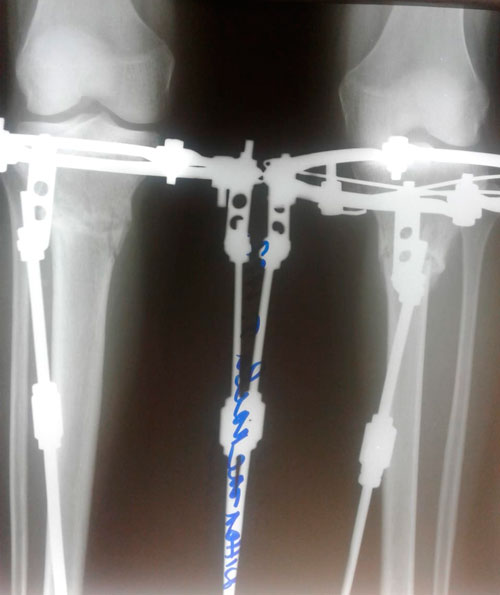

Перед крутками.

Вложения

IMG_0786-31-01-19-10-50.JPG